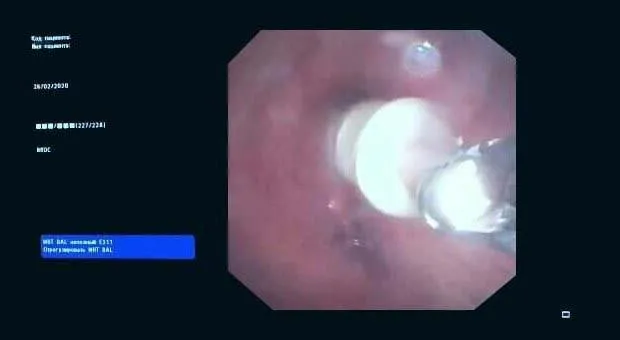

Вчера в отделении эндоскопии успешно апробировано окклюзия бронхоплеврального свища.

Пациент К. 1960 г.р., после правосторонней пульмонэктомии от 2019 г. поступил в отделение многоплановой хирургии. При плановой бронхоскопии выявлена несостоятельность культи правого главного бронха, устье свища до 0.3 см, откуда поступает слизисто-гнойное содержимое. В устье свища определяется сшивающая скоба. Также у пациента имеется дренажная трубка справа в 7 межреберье, подключаемая к активному отсосу.

Во время повторной бронхоскопии под интубационным наркозом установлен окклюдер из ИМН другого назначения (PULL THRU) в устье свища. Поперечные резиновые лепестки на окклюдере и скоба в устье свища должны надёжно фиксировать положение окклюдера.

Оборудование: видеобронхоскоп Olympus 180, окклюдер PULL THRU( Medivators)